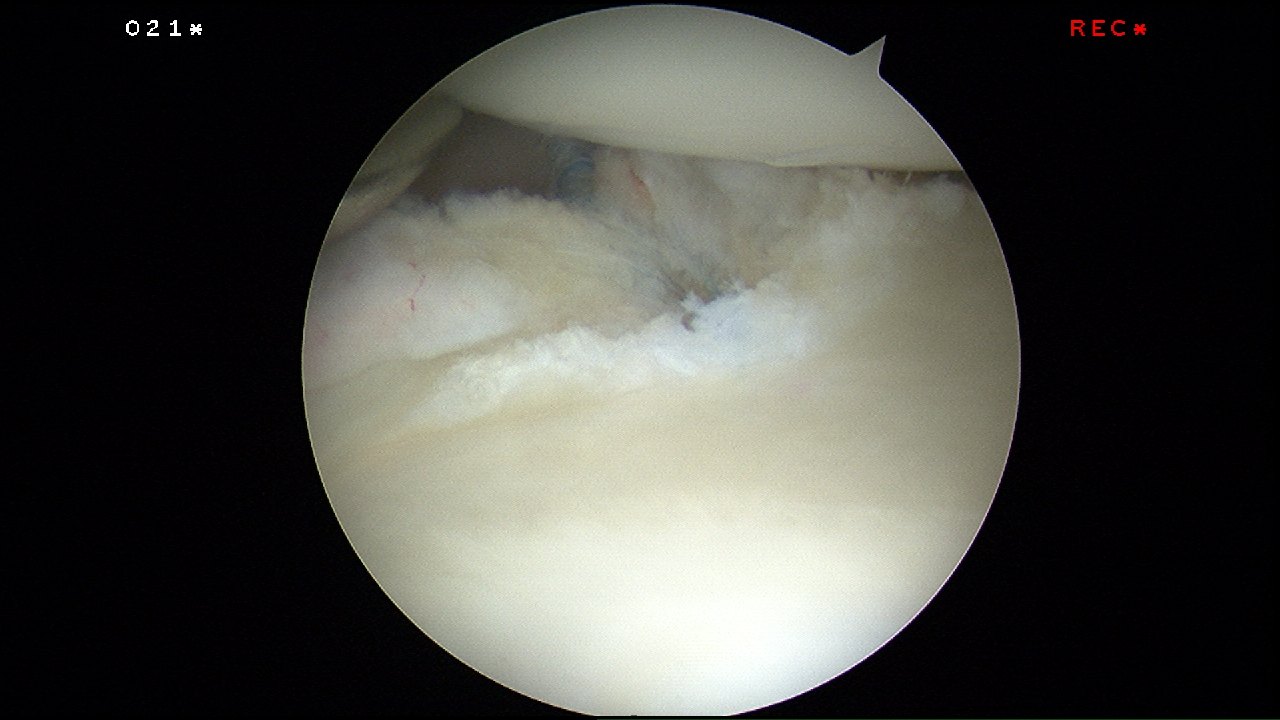

The sutures are passed around the labral tear using a shuttle suture (blue).

The suture is looped around the torn labrum and ready for tying.

The sutures are tied and the labral tear is reattached to the posteroinferior glenoid labrum.

This is how it looks like post-repair –